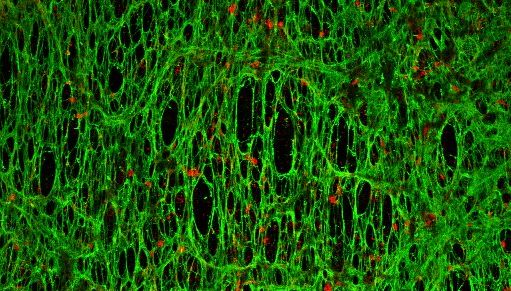

A dnes už vím, že některé vlastnosti nádoru mohou léčebnou účinnost nanočástic ovlivnit. Třeba nadměrný extracelulární matrix, tedy mimobuněčná hmota, která se nachází mezi buňkami tkání. V místě nádoru může tedy fungovat jako fyzická bariéra, která brání pronikání léčiva. Chci studovat, jak nanočástice s různými složkami nádorového mikroprostředí interagují. Projekt, na kterém teď pracuji, by měl identifikovat vlastnosti nanočástic, které umožní lepší průnik, a tím pádem účinnější distribuci léčiva. Věnuji se léčbě zaměřené přímo na extracelulární matrix a jeho hlavní producenty – fibroblasty.

Nejjednodušeji se nanočástice pozorují pomocí fluorescenčního značení. Pokud zbarvíme jejich povrch nebo vnitřek, můžeme sledovat jejich pohyb uvnitř buněk nebo uvnitř tkání laboratorních myší.

Co se týče vědecké práce, chci popsat, jak nanočástice interagují s mikroprostředím nádoru a popsat konkrétní vlastnosti, které by měly mít, aby se nezdržovaly ve fibrózním extracelulárním matrixu a mohly efektivně proniknout do nádoru a ničit tak rakovinné buňky. Případně zjistit, jakým způsobem modulovat extracelulární matrix. Tady v Melbourne mám k dispozici materiálovou expertizu a v Brně organoidní modely a pacientské tkáně, můžu to tak testovat přímo na nich, to je obrovský krok kupředu.